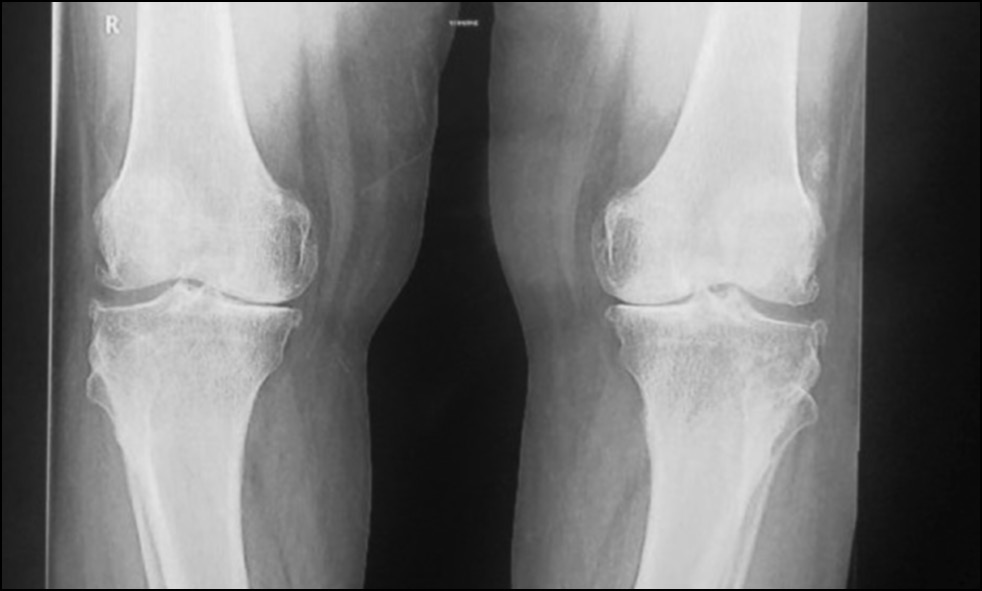

CASE 1. PATIENT 16

Age: 64 years.

Sex: Female.

Diagnosis: Bilateral advanced knee osteoarthritis.

Procedure: Bilateral simultaneous knee arthroplasty.

Associated illnesses: Hypertension.

Postoperative follow-up: No postoperative complications were encountered.

Length of hospital stay: 6 days.

Radiological assessment (Fig. 11–14)

Fig. 11. Ap preoperative x-ray showing bilateral knee osteoarthritis.

Рис. 11. Предоперационная рентгенограмма с двусторонним остеоартритом коленного сустава.